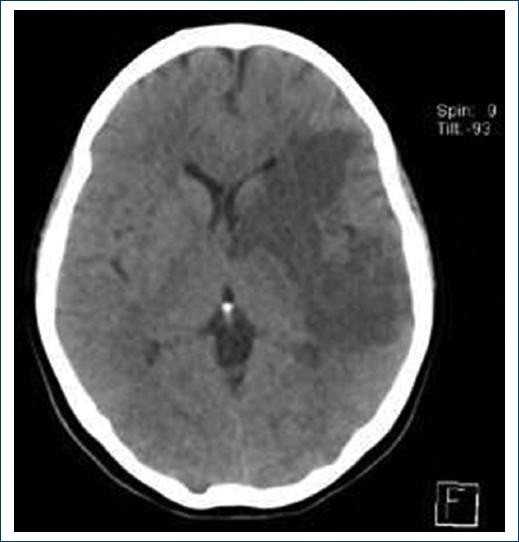

The computed tomography (CT) image of the simple skull shows that; ischemic cerebral infarction in the subacute phase located in the left hemisphere with involvement of the temporal lobe, inferior frontal gyrus, deep area of the semioval center, lenticular nucleus, dorsolateral portion of the head of the caudate nucleus, anterior arm and knee of the internal capsule, rostral area of the thalamus and short gyrus of the insula, exerts a slight effect on volume and obliterates the corresponding gyrus (Fig. 1).

Figure 1 Ischemic cerebral infarction in the subacute phase located in the left hemisphere with temporal lobe involvement.